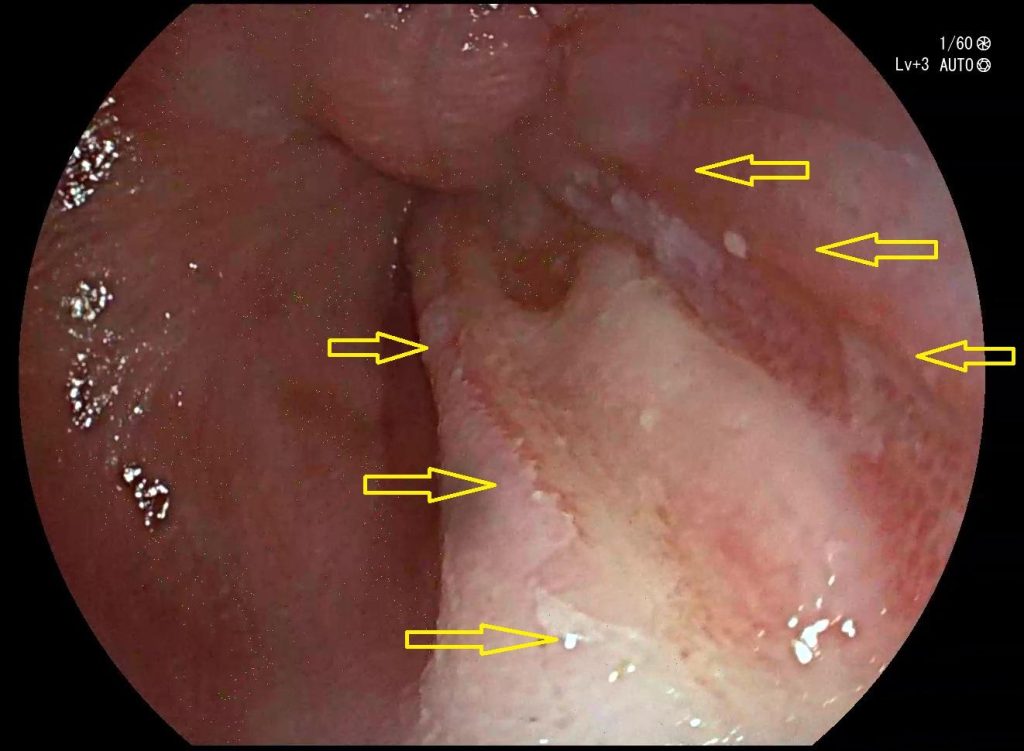

Esofagitis grave por reflujo biliar

Gastritis Crónica

La exposición prolongada de la mucosa gástrica a la bilis puede llevar a una inflamación crónica, que a su vez puede aumentar la probabilidad de desarrollar otras complicaciones. Estas complicaciones son más frecuentes en pacientes con cirugías previas del tracto gastrointestinal superior y en aquellos con exposición prolongada a la bilis.

Metaplasia intestinal alrededor del píloro en el reflujo biliar duodenogástrico. Imagen de cromoendoscopia digital.

Entre las posibles complicaciones que se pueden desarrollar se encuentran:

• Desarrollo de lesiones gástricas preneoplásicas: progresión de gastritis atrófica a metaplasia intestinal y displasia que ven acelerada su evolución hacia el cáncer gástrico por la presencia de reflujo biliar.

• Úlceras gástricas.

• Alteraciones funcionales como el deterioro de la motilidad gástrica, los trastornos de la secreción ácida, la alteración de la barrera mucosa o la malabsorción de algunos nutrientes.

• Complicaciones sistémicas: Son infrecuentes, pero puedes desarrollar anemia por malabsorción, deficiencias nutricionales, o pérdida de peso.